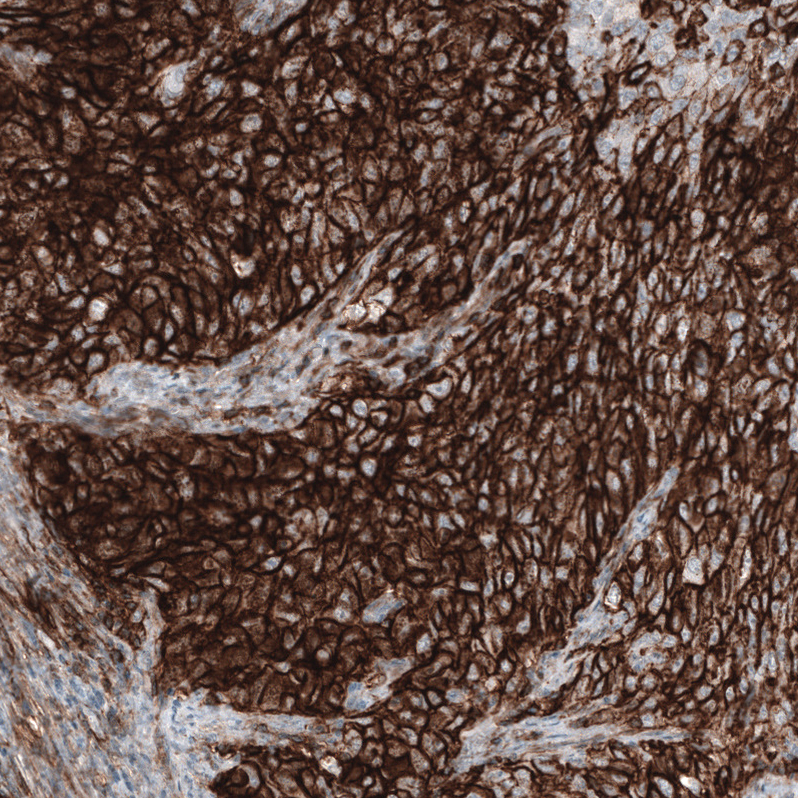

Immunohistochemistry analysis in human cervix, uterine and skeletal muscle tissues using AMAb91845 antibody. Corresponding CD44 RNA-seq data are presented for the same tissues.